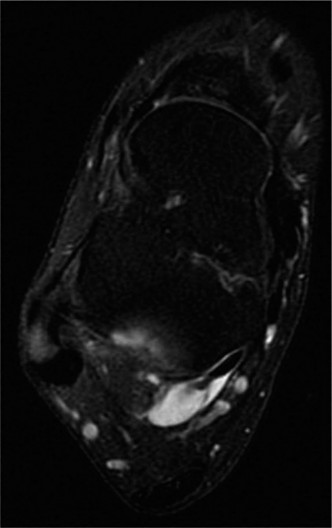

A 16-year-old female sprains her ankle playing lacrosse and is brought to the emergency room. X-rays are nega…